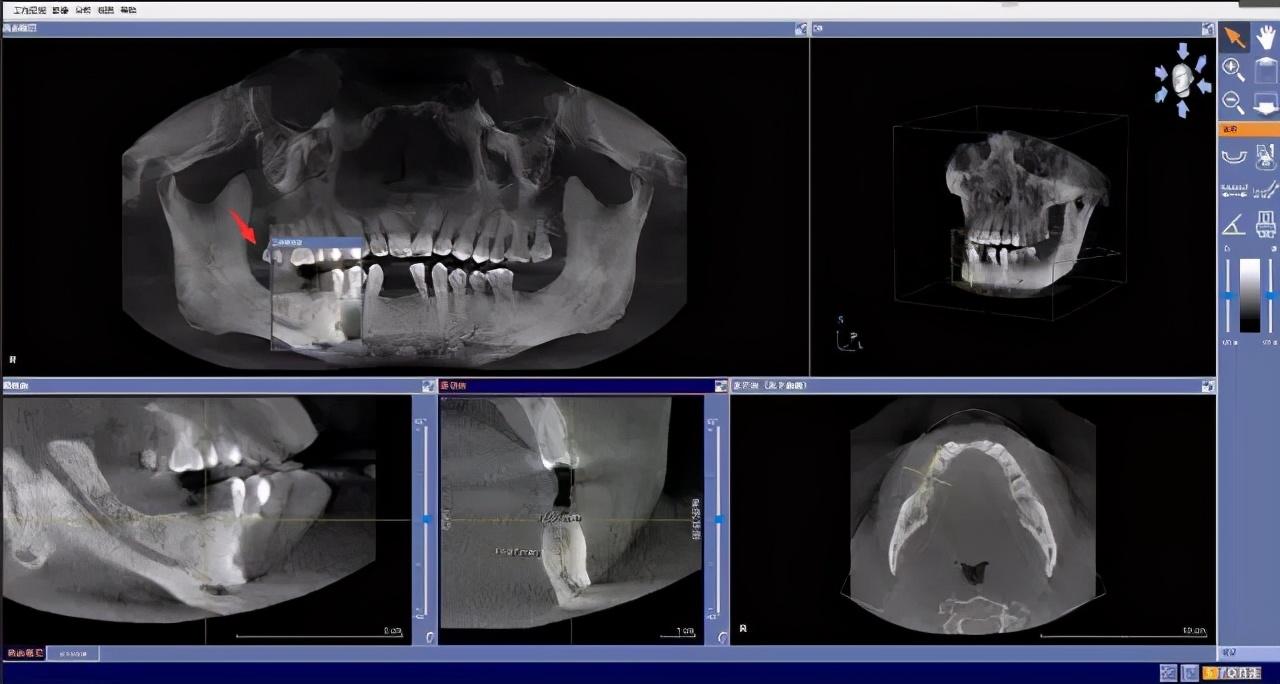

step1

先要做一個口腔全景片、頜骨CT等

醫(yī)生根據(jù)機(jī)器成像查看口腔的具體情況,

是否有炎癥、牙槽骨的密度、吸收狀況

以及鄰牙組織、牙體組織等。

注明:此數(shù)據(jù)僅作模擬,不是確切種植數(shù)據(jù)。

如果僅靠雙眼大致估測口內(nèi)數(shù)據(jù),是無法得到的高度、寬度的,也無法確認(rèn)骨頭吸收多少,是否需要植入骨粉。

對后期手術(shù)有一定的影響。

通過全景片可以“解剖”牙齒測量,適宜的種植角度也可確定,健康有保障。